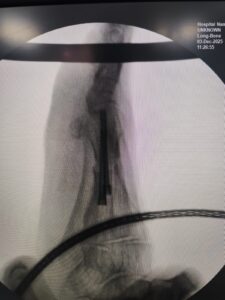

Minimally invasive foot surgery is an advanced surgical technique performed through very small incisions using specialized instruments and imaging guidance. Unlike conventional surgery, MIS reduces trauma to surrounding muscles and tissues, resulting in less pain, minimal scarring, and faster healing.

Certain fractures and tendon issues

Accurate diagnosis using modern imaging

Advanced MIS techniques